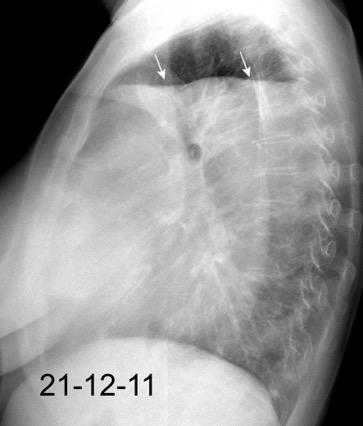

Accidente de tráfico

Rx: Niveles hidroaéreos en hemitórax izquierdo Desviación mediastínica Ausencia de intestino en abdomen. Configuración en reloj de arena del intestino herniado “Tubo nasogástrico”

Furak J et al. Diaphragm and transdiaphragmatic injuries. J Thorac Dis 2019

Recibe una puñalada en costado izquierdo

La laceración tiende a ocurrir en la unión

músculotendinosa . (64-90% en el lado izquierdo)

Diafragma “colgante” (“dangling sign”)

(“Dangling sign”)

TC. Mejor con multicorte. (reconstrucciones).

Asociación: Aire en pared.

Fracturas costal .Rotura esplénica. Neumoperitoneo.

Diafragma discontinúo Herniación de la grasa omental

Desser TS et al.The dangling diaphragm sign: sensitivity and comparison with existing CT signs of blunt traumatic diaphragmatic rupture. Emerg Radiol 2010